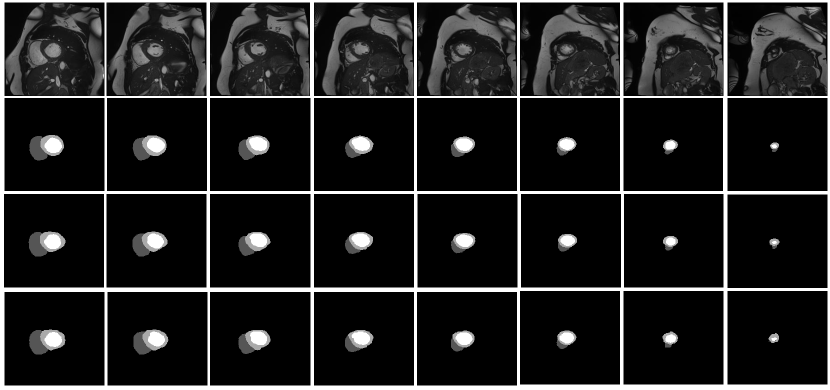

Refer to caption

Figure 4: Segmentation Results for a full MR image (Complete Phase) from slices 0-8 . First Row: Raw MR input images Second Row: Corresponding ground truth annotations. Third Row: Output predictions from 2D segmentation model. Fourth Row: Output predictions from 3D segmentation model.